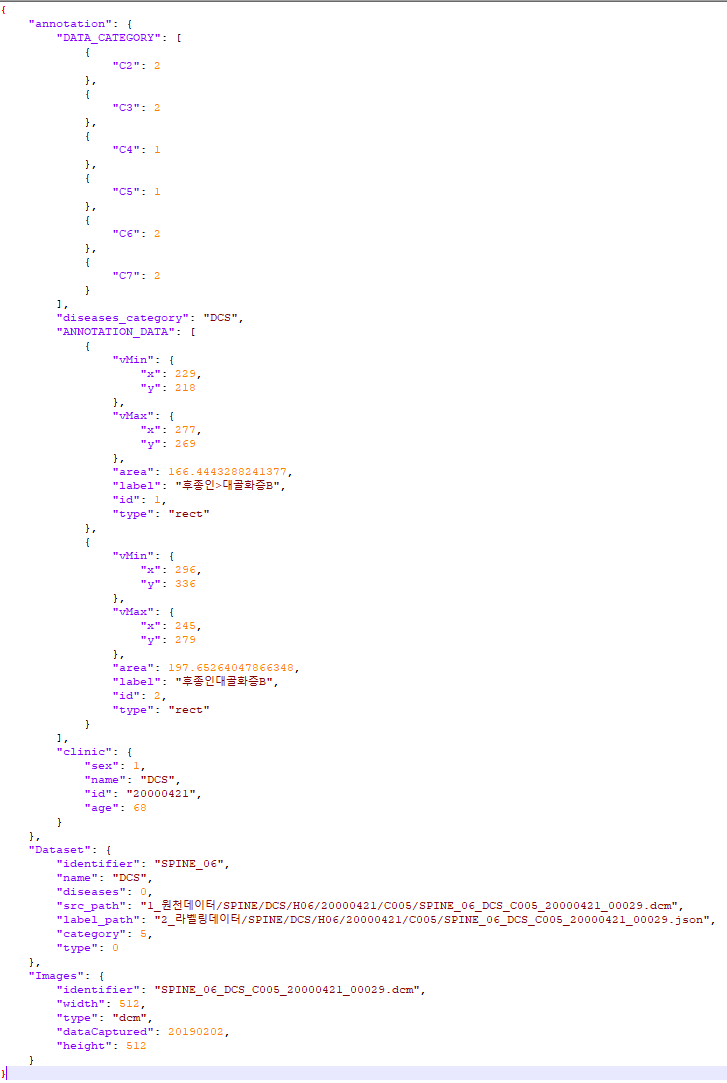

데이터 포맷 dicom 포맷, json 포맷 dicom 포맷, json 포맷 dicom 포맷, json 포맷 - DCS 라벨링데이터 실제예시

- Json 형식

- 속성 정의

DCS 라벨링데이터 실제예시 속성 정의 No 항목 길이 타입 필수여부 한글명 영문명 1 어노테이션 정보 annotation Object 1–1 데이터 분류 DATA_CATEGORY Array 1–1–1 후종인대 C2 유무 C2 Number 1–1–2 후종인대 C3 유무 C3 Number 1–1–3 후종인대 C4 유무 C4 Number 1–1–4 후종인대 C5 유무 C5 Number 1–1–5 후종인대 C6 유무 C6 Number 1–1–6 후종인대 C7 유무 C7 Number 1–1–7 탈출증 유무 C3-4 유무 C34 Number 1–1–8 탈출증 유무 C4-5 유무 C45 Number 1–1–9 탈출증 유무 C5-6 유무 C56 Number 1–1–10 탈출증 유무 C6-7 유무 C67 Number 1–1–11 추간판 탈출증 C3-4 유무 C34disk Number 1–1–12 추간판 탈출증 C4-5 유무 C45disk Number 1–1–13 추간판 탈출증 C5-6 유무 C56disk Number 1–1–14 추간판 탈출증 C6-7 유무 C67disk Number 1–2 어노테이션 질병분류 disease_category String Y 1–3 어노테이션 결과 데이터 ANNOTATION_DATA Array 1–3–1 저작도구 식별자 id Number 1–3–2 저작도구 타입 type String 1–3–3 라벨 label String 1–3–4 사각형 시작점 vMin Object 1–3–4–1 사각형 시작점 x 좌표 x Number 1–3–4–2 사각형 시작점 y 좌표 y Number 1–3–5 사각형 끝점 vMax Object 1–3–5–1 사각형 끝점 x 좌표 x Number 1–3–5–2 사각형 끝점 y 좌표 y Number 1–3–6 면적 area Number 1–3–7 거리 distMm Number 1–3–8 시작점 vs Object 1–3–8–1 시작점 x 좌표 x Number 1–3–8–2 시작점 y 좌표 y Number 1–3–9 끝점 ve Object 1–3–9–1 끝점 x 좌표 x Number 1–3–9–2 끝점 y 좌표 y Number 1–3–10 각도 angle Number 1–3–11 점 좌표 points Array 1–3–11–1 점 x 좌표 x Number 1–3–11–2 점 y 좌표 y Number 1–3–12 폴리건 범위 m_area Number 1–3–13 폴리건 범위 좌표 m_points Array 1–3–13–1 폴리건 범위 x좌표 x Number 1–3–13–2 폴리건 범위 y좌표 y Number 1–3–14 폴리건 개방 여부 m_isClosed Boolean 1–4 임상의료데이터 clinic Object Y 1–4–1 식별자 id String Y 1–4–2 진단명 name String Y 1–4–3 나이 age Number Y 1–4–4 성별 sex Number Y 2 데이터셋 정보 Dataset Object Y 2–1 데이터셋 식별자 identifier String Y 2–2 데이터셋 이름 name String Y 2–3 데이터셋 폴더 위치 src_path String Y 2–4 데이터셋 레이블 폴더 위치 label_path String Y 2–5 데이터셋 질병분류 diseases Number Y 2–6 데이터셋 카테고리 category Number Y 2–7 데이터셋 타입 type Number Y 3 이미지정보 Images Object 3–1 이미지 식별자 (파일명) identifier String 3–2 이미지 파일 확장자 type String 3–3 이미지 가로 크기 (픽셀) width Number 3–4 이미지 세로 크기 (픽셀) height Number 3–5 이미지 생성 일자 dataCaptured String

- Json 형식